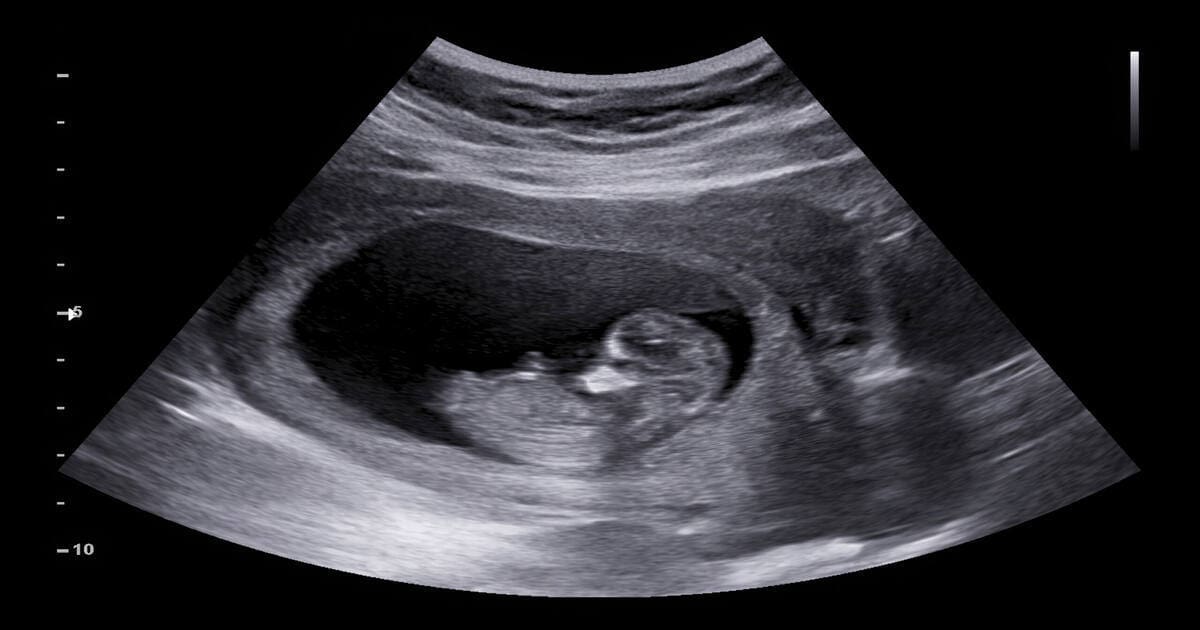

Child Stolen From Hospital: ಹೆರಿಗೆಗೆಂದು ಬಂದಿದ್ದ ಮಹಿಳೆಯೋರ್ವಳು ಮಕ್ಕಳ ಕಳ್ಳತನ ಆರೋಪ ಮಾಡಿ ಗಲಾಟೆ ಮಾಡಿದ ಘಟನೆಯೊಂದು ನಡೆದಿದೆ. ಉತ್ತರ ಪ್ರದೇಶದ ಬಸ್ತಿಯಾ ಮಹಿಳಾ ಆಸ್ಪತ್ರೆಯಲ್ಲಿ ಭಾನುವಾರ ಈ ಘಟನೆ ನಡೆದಿದೆ. ಅಲ್ಟ್ರಾಸೌಂಡ್ ವರದಿಯಲ್ಲಿ ಮಹಿಳೆ ಅವಳಿ ಮಕ್ಕಳನ್ನು ಹೊಂದಿದ್ದಾಗಿ ದೃಢಪಡಿಸಿರುವುದಾಗಿ ಕುಟುಂಬ ಸದಸ್ಯರು ಆರೋಪ ಮಾಡಿದ್ದಾರೆ. ಆದರೆ ಹೆರಿಗೆಯ ನಂತರ ಆಸ್ಪತ್ರೆಯ ಸಿಬ್ಬಂದಿ ಒಂದು ಮಗು ಕಾಣೆಯಾಗಿ ಎಂದು ಮಹಿಳೆ ಆರೋಪ ಮಾಡಿದ್ದಾರೆ. ಈ ಬಗ್ಗೆ ಗರ್ಭಿಣಿಯ ಪತಿ ಆಸ್ಪತ್ರೆಯ ಸಿಎಂಎಸ್ಗೂ ದೂರು ನೀಡಿದ್ದಾರೆ.

ಮತ್ತೊಂದೆಡೆ, ಹೆರಿಗೆಗೂ ಮುನ್ನ ಪತ್ನಿಯ ಅಲ್ಟ್ರಾಸೌಂಡ್ ಮಾಡಿಸಿದ್ದಾಗಿ ಗರ್ಭಿಣಿಯ ಪತಿ ರಮೇಶ್ ಕುಮಾರ್ ಹೇಳಿದ್ದಾರೆ. ಗರ್ಭದಲ್ಲಿ ಅವಳಿ ಮಕ್ಕಳಿರುವುದು ಬೆಳಕಿಗೆ ಬಂದಿದೆ. ಗರ್ಭದಲ್ಲಿ ಅವಳಿ ಮಕ್ಕಳಿರುವ ಕಾರಣ ಕೆಲವು ಸಮಸ್ಯೆಗಳಿವೆ ಎಂದು ತಿಳಿಸಿದರು. ಈ ಸಮಸ್ಯೆಗಳನ್ನು ಗಮನದಲ್ಲಿಟ್ಟುಕೊಂಡು ಮಹಿಳಾ ಆಸ್ಪತ್ರೆಯ ವೈದ್ಯರು ಹೆರಿಗೆಯನ್ನೂ ನಡೆಸಿದ್ದು, ಒಂದು ಮಗುವನ್ನು ಮಾತ್ರ ಅವರಿಗೆ ಹಸ್ತಾಂತರಿಸಲಾಗಿದೆ.

ಡಿ.29 ರಂದು ಹೆರಿಗೆಗಾಗಿ ತನ್ನ ಪತ್ನಿ ರೇಖಾ ಮಹಿಳಾ ಆಸ್ಪತ್ರೆಗೆ ದಾಖಲಾಗಿದ್ದರು. ಅದೇ ದಿನ ಸಂಜೆ ತಡವಾಗಿ ಪತ್ನಿಗೆ ಹೆರಿಗೆ ಮಾಡಲಾಯಿತು. ನಂತರ ವೈದ್ಯರು ಒಂದೇ ಮಗು ಜನಿಸಿರುವುದಾಗಿ ತಿಳಿಸಿದರು. ಈ ಹಿಂದೆ ನಡೆಸಿದ ಅಲ್ಟ್ರಾಸೌಂಡ್ ವರದಿಯಲ್ಲಿ ನಮಗೆ ಅವಳಿ ಮಗು ಇರುವುದು ದೃಢಪಟ್ಟಿತ್ತು ಎಂದು ಮಗುವಿನ ತಂದೆ ರಮೇಶ್ ಕುಮಾರ್ ಹೇಳಿದ್ದಾರೆ. ಆಸ್ಪತ್ರೆ ಸಿಬ್ಬಂದಿ ಅಪರೇಷನ್ ಥಿಯೇಟರ್ನಿಂದ ಎರಡನೇ ಮಗುವನ್ನು ಕದ್ದು ನಾಪತ್ತೆಯಾಗಿದ್ದಾರೆ ಎಂದು ಅವರು ಆರೋಪ ಮಾಡಿದರು.